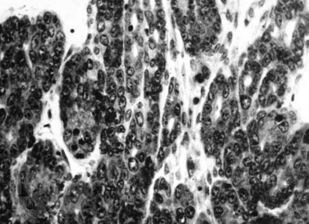

Книга посвящена описанию животных моделей in vivo для отбора, углубленного и/или доклинического изучения цитостатиков, а также некоторых таргетных средств. Представлены основные биологические характеристики, дополненные лекарственной чувствительностью и востребованностью в настоящее время.